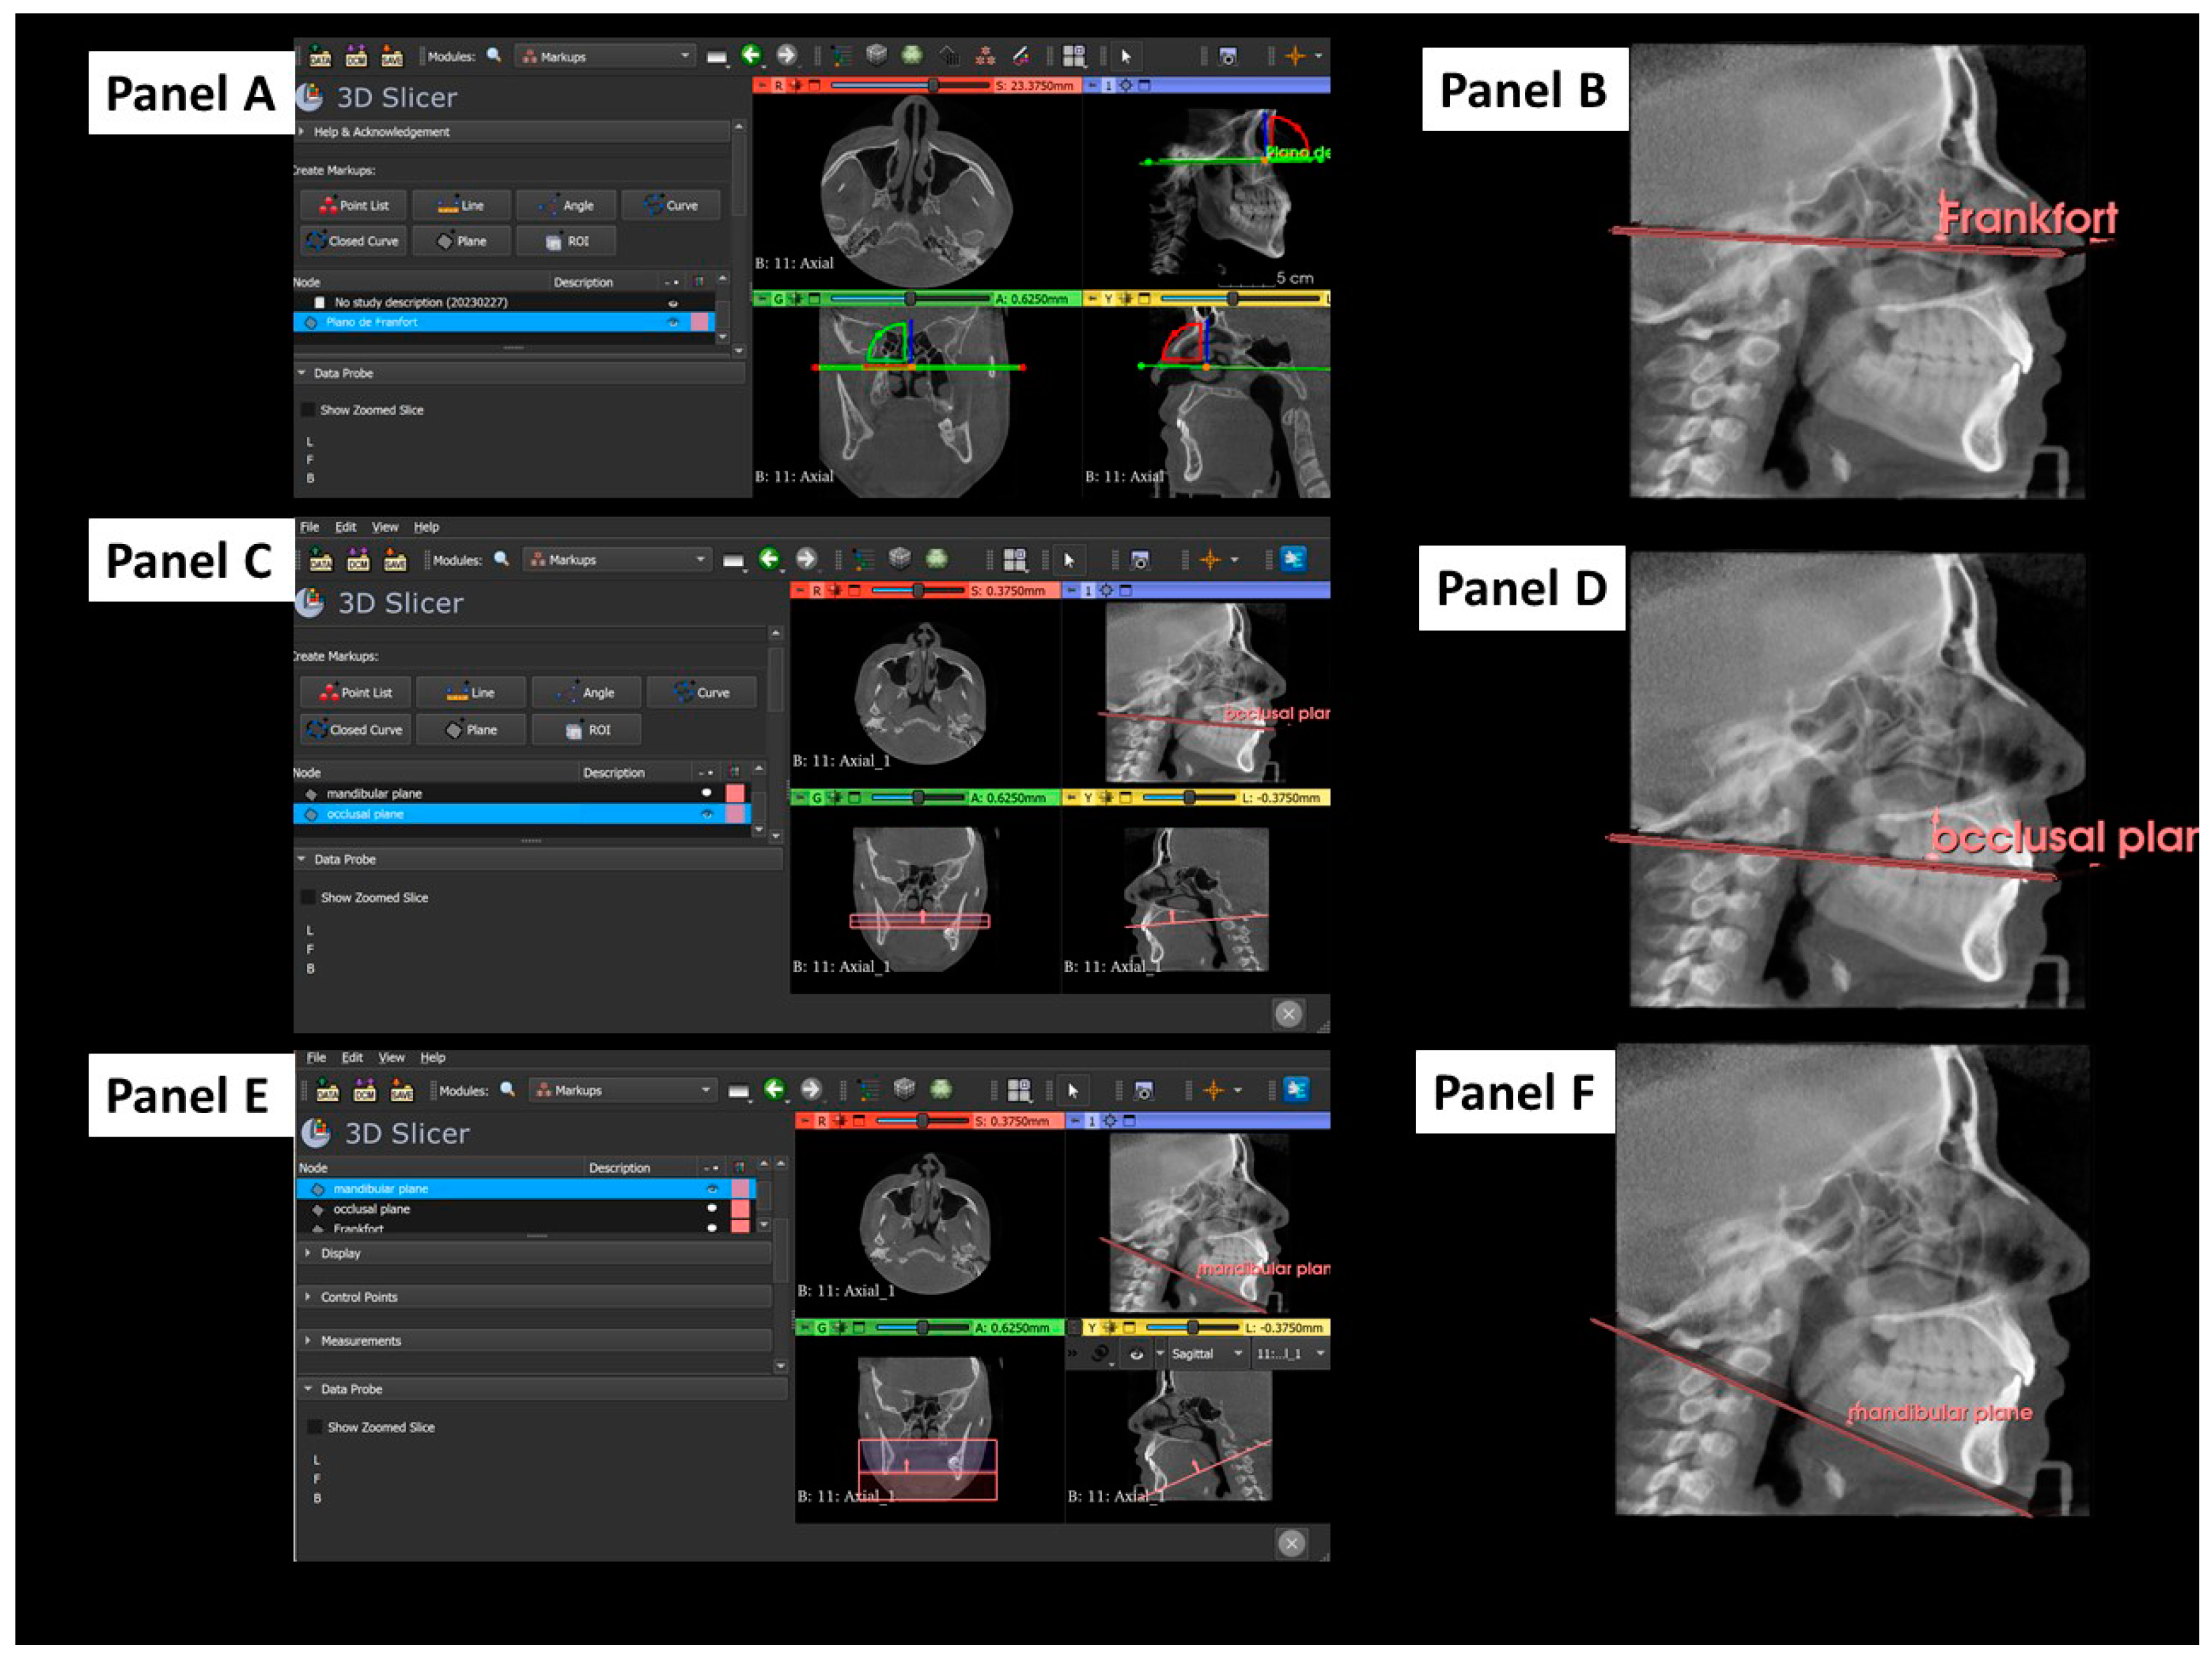

2.3. Tridimensional Reference Planes

2.4. Outcome and Independent Variables

2.5. Cephalometric 2D Variables